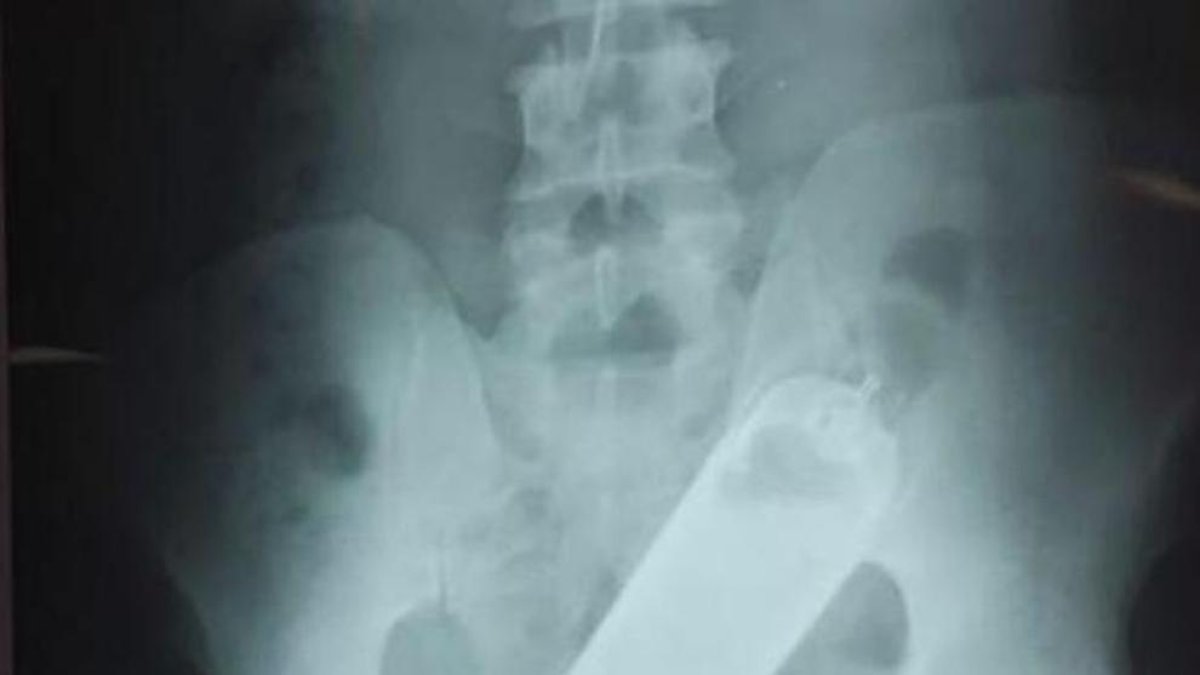

Primero interrogaron al paciente y después le realizaron una radiografía, que reveló que el hombre tenía un frasco en el recto. Posteriormente, los médicos formaron un equipo de especialistas para extraerle en el quirófano el frasco, que estaba dentro de un condón, precisó al portavoz del hospital.